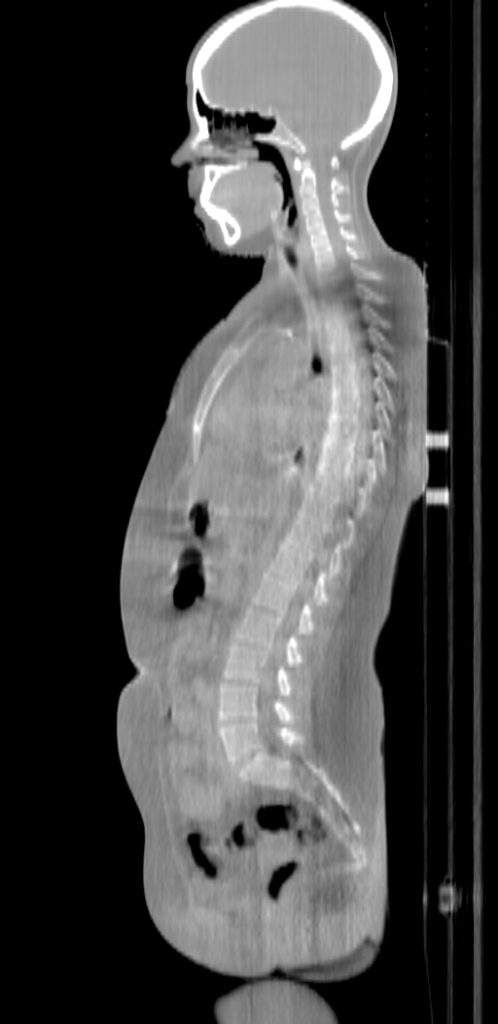

ClearRT® Images

Imaging Information

ClearRT®

Protocol

Whole body-mediumFOV 50cm

Scan Length

75cm

KVCT Imaging Time

1 min